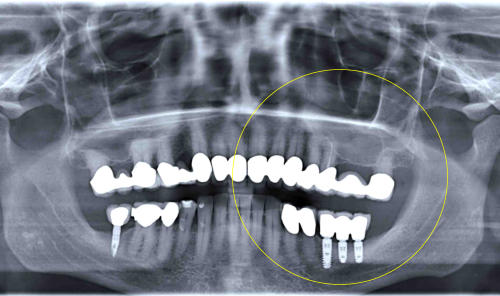

mit Kronen versorgte Implantate